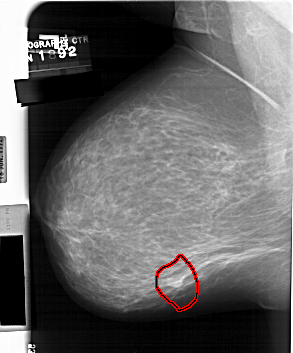

FILE: A_1560_1.LEFT_MLO.OVERLAY

TOTAL_ABNORMALITIES 1

ABNORMALITY 1

LESION_TYPE MASS SHAPE LOBULATED MARGINS OBSCURED

ASSESSMENT 4

SUBTLETY 4

PATHOLOGY BENIGN

TOTAL_OUTLINES 1

BOUNDARY